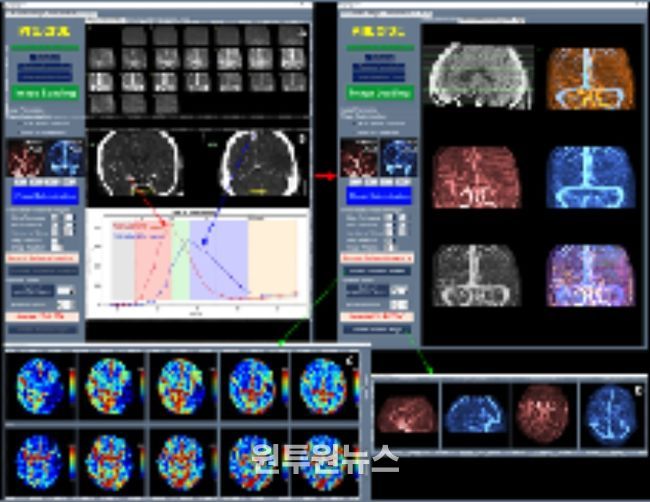

이와 함께 허혈성 뇌혈관 질환 환자를 대상으로 혈관재개통 치료가 필요한 환자 선별을 지원하는 소프트웨어 등 다양한 진단·치료 보조 AI 의료기기들이 혁신의료기기로 지정됐다.